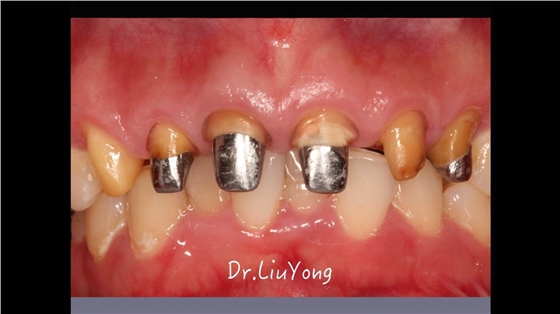

嚴重破壞生物學寬度,根尖瘺管,重行根管治療,第一次冠延長建立唇腭側及鄰面BW, 術后牙齦扇貝形差,齦乳頭黑三角,再次行美學冠延長,建立牙齦扇貝形,手術免費, 患者因經濟原因只能選擇鑄樁及鈷鉻合金烤瓷冠。終于完工